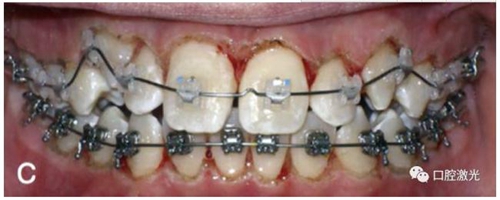

有時,會遇到一些口腔衛(wèi)生問題比較嚴重的患者,從而導致牙齦發(fā)炎而腫大。通過改善口腔衛(wèi)生環(huán)境,炎癥可以得到緩解,但增生的牙齦不一定都可以完全恢復。下圖的患者就存在口腔牙齦肥厚問題,同時左上部犬牙存在部分萌出的問題,右上部犬牙存在未萌出問題,這些問題都妨礙了托槽的粘接。因此,實施了全口腔的牙齦整形手術(shù)。去除了多余的牙齦組織,增加了犬牙的暴露面積,從而使托槽的粘接更為便利,同時也提升了患者保持口腔衛(wèi)生的狀況。

治療前

激光牙齦整形后即刻

激光治療當天粘接托槽

6周后效果